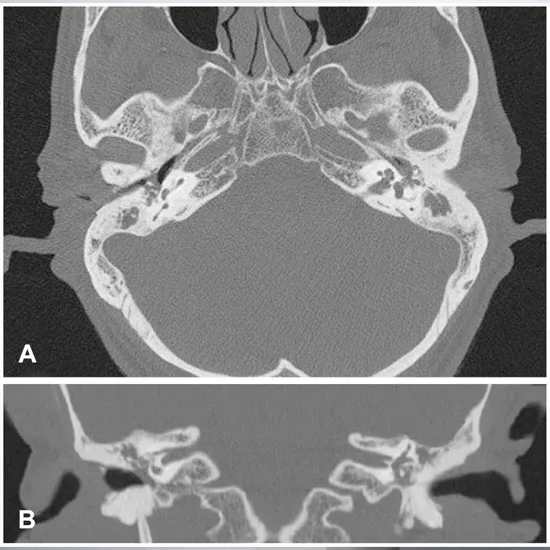

CECT Inner Ear (Axial and Coronal) acronyms for Contrast Enhanced Computed Tomography for the inner ear at both axial and coronal plain. To diagnose/detect inner ear problems, the doctor recommends this scan. For this scan, contrast media, an X-ray beam, and a computer are used to obtain pictures of the inner eyes. It helps diagnose the malformation in the inner ear.

CECT (Contrast-enhanced computed tomography) screening of the Inner Ear is a non-invasive radiology test used to evaluate the condition of the Inner Ear and surrounding tissue. CECT Inner Ear is done to look for the conditions of the Inner Ear and the surrounding area.